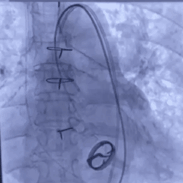

3. 术中实行的20球囊的预扩,AV26瓣膜的释放,瓣膜释放后发现还有展开的余地,故进一步选择23的球囊进行后扩使人工瓣膜更贴合主动脉根部结构。

23mm球囊后扩张

瓣膜释放后造影评估

术后压差从46mmHg降至6mmHg

术后超声心动图提示:主动脉瓣人工瓣膜前向1.9m/s,平均垮瓣压差约6mmHg,微量反流,左室壁博幅正常范围,心包未见积液,手术效果良好。